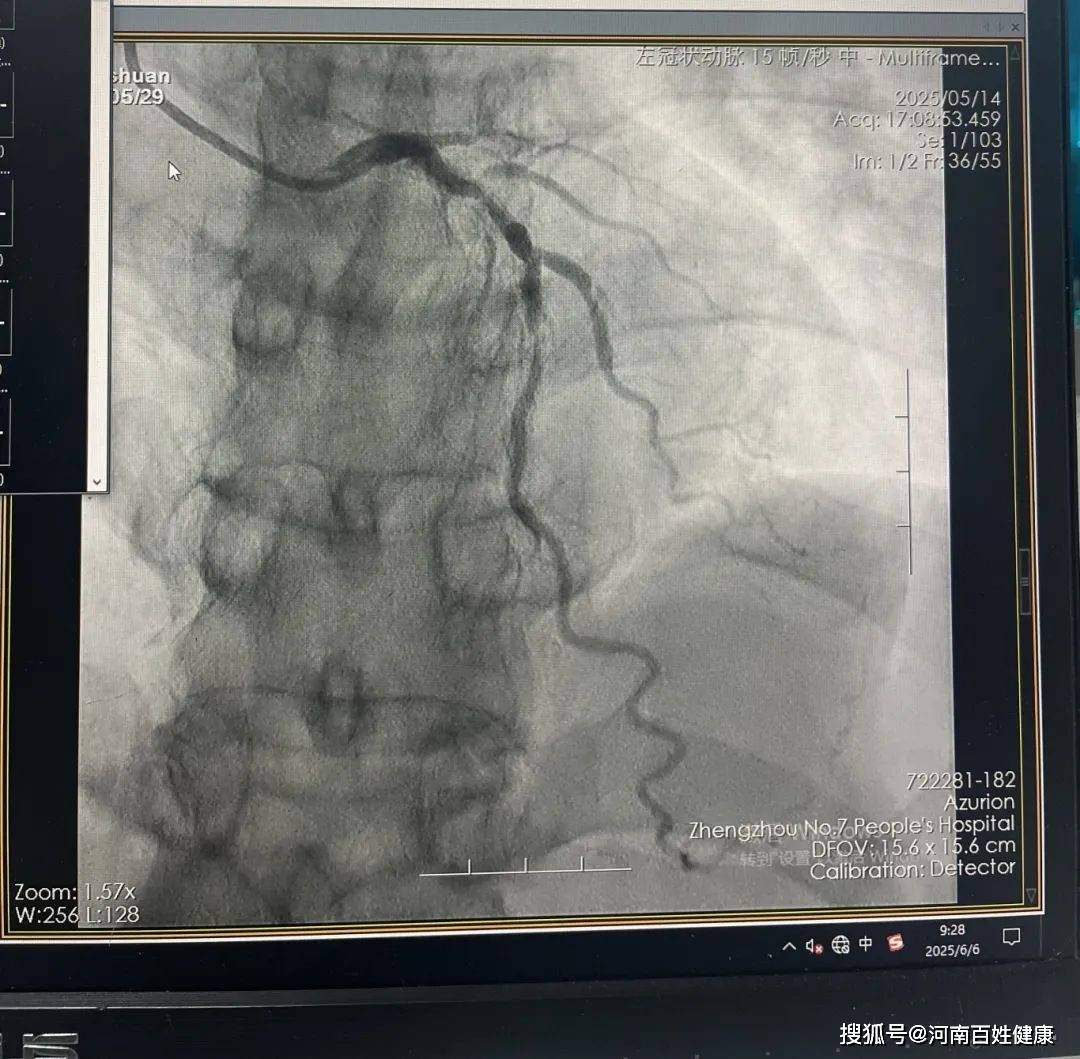

冠状动脉造影显示,他的支架内出现了严重的内膜增生,血管狭窄程度超过80%,这意味着传统治疗手段可能面临“束手无策”的困境。

(术前支架内狭窄严重)